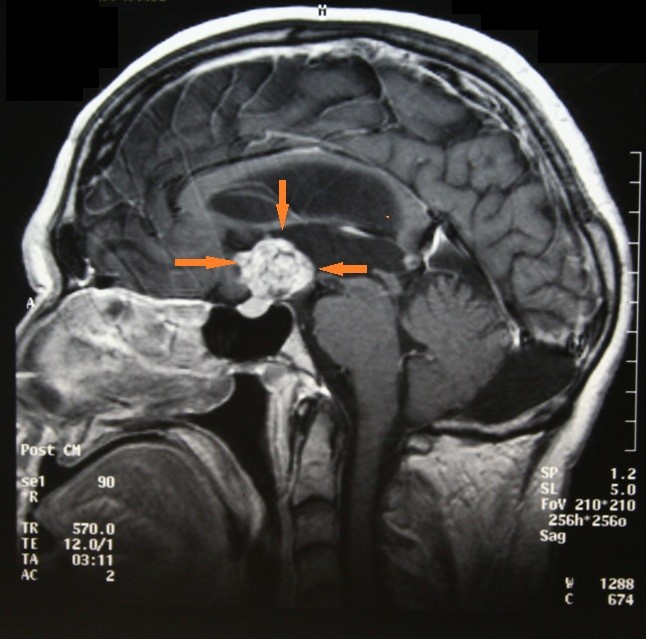

I began researching this project in June 2013 after marrying my wife, Pam, who has been a steadfast supporter, cheering me on along the way. I obtained medical records dating back to 1984 and incorporated journal entries from the early 1990s. So in many ways, I’ve been writing this memoir my whole life. The impetus to write the book sprang from a long blog post I wrote in December 2014 to mark the 30th anniversary of my initial brain surgery at SUNY Upstate Medical University Hospital in Syracuse, New York.

Set between 1984 and the mid–1990s, this coming-of-age memoir follows Francis DiClemente’s experience of adolescence and early adulthood in a body that struggled to develop. Diagnosed with a rare brain tumor that led to hypopituitarism, DiClemente remained physically underdeveloped while his peers matured into young adulthood. As he navigated relationships and sexuality in college, it became evident that his prolonged experience with physical nonconformity fueled isolation, self-doubt, and shame.

“DiClemente delivers an unflinching account of the brain tumor that disrupted normal growth and his participation in one of the first human growth hormone trials. …a touching and compelling memoir.”